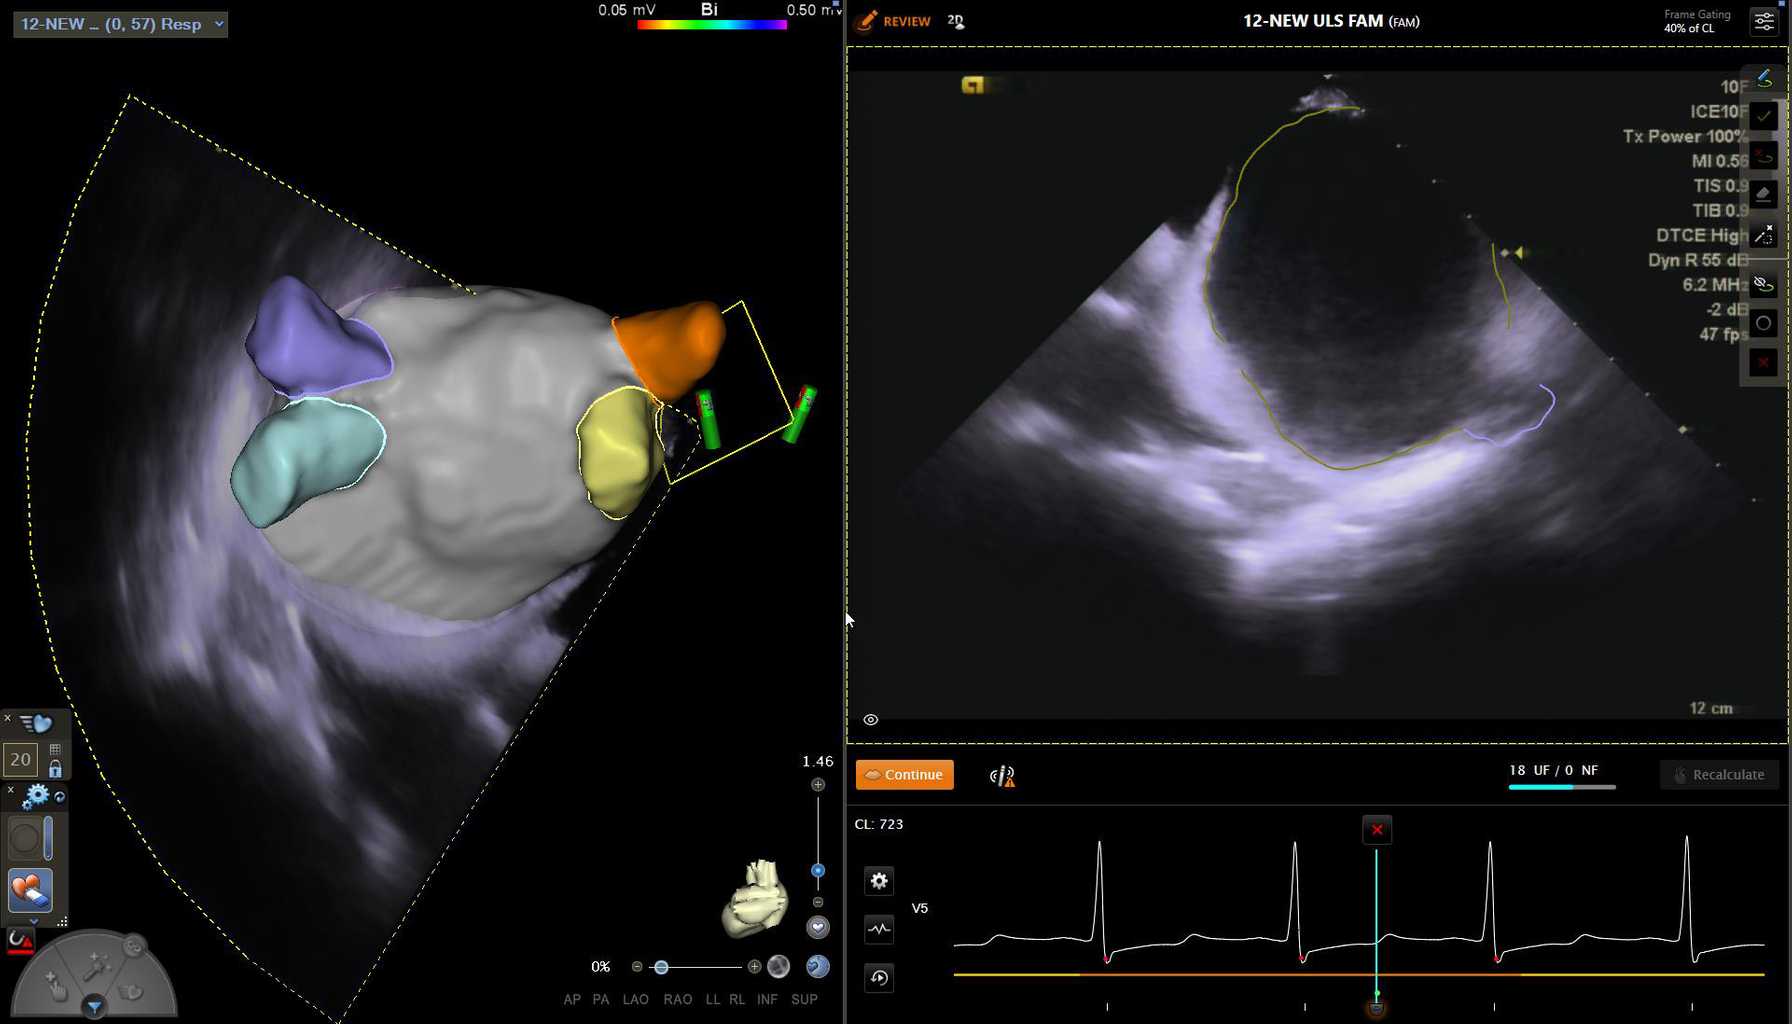

In 2024, Montefiore Einstein Cardiology advanced its leadership in cardiac care and research, making groundbreaking strides in heart transplantation, structural valve interventions and arrhythmia management, while also expanding its state-of-the-art imaging program. This commitment to innovation, alongside significant contributions to scientific research and global education, underscores Montefiore Einstein's dedication to providing the highest quality of care.

Cardiac arrythmias

6,964

Diag, int and structural

Imaging